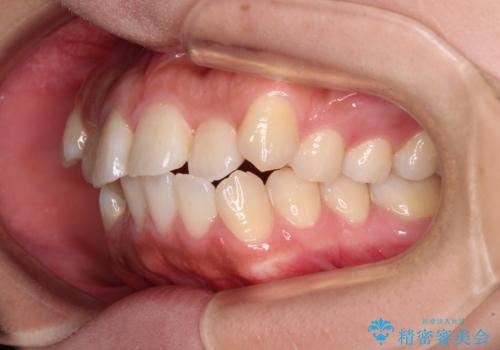

- 前歯の出っ歯と口元の閉じにくさを気にして来院された患者様です。

口元を積極的に引っ込めるために、上下左右の小臼歯4本を抜歯することとしました。